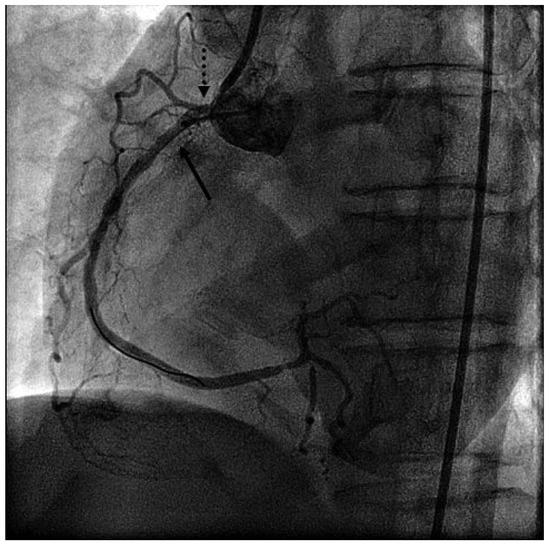

Early Morning Recurrent Chest Pain

by Silke Maile, Igal Moarof and Marc Michot

The differential diagnosis of recurrent chest pain is manifold. Although it is unlikely in younger people, a cardiac origin should always be considered. We report a case of recurrent chest pain which was initially considered to have a gastrointestinal or psychic origin. A [...] Read more.

The differential diagnosis of recurrent chest pain is manifold. Although it is unlikely in younger people, a cardiac origin should always be considered. We report a case of recurrent chest pain which was initially considered to have a gastrointestinal or psychic origin. A circadian pattern of the pain was conspicuous. Finally, coronary angiography performed in the setting of an acute coronary syndrome followed by life-threatening rhythm disturbances established the diagnosis. Full article